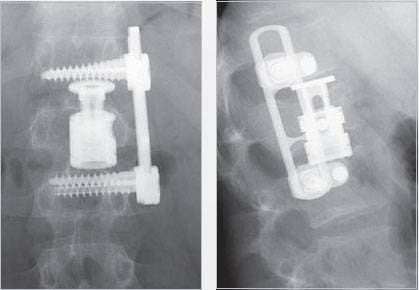

Спондилоптоз L5. Двухэтапная операция - резекция тела L5 и фиксация пояснично-крестцового отдела (L3-L4-S1) системой CDI и TSRH, межтеловой спондилодез L4-S1 кейджами Interfix.